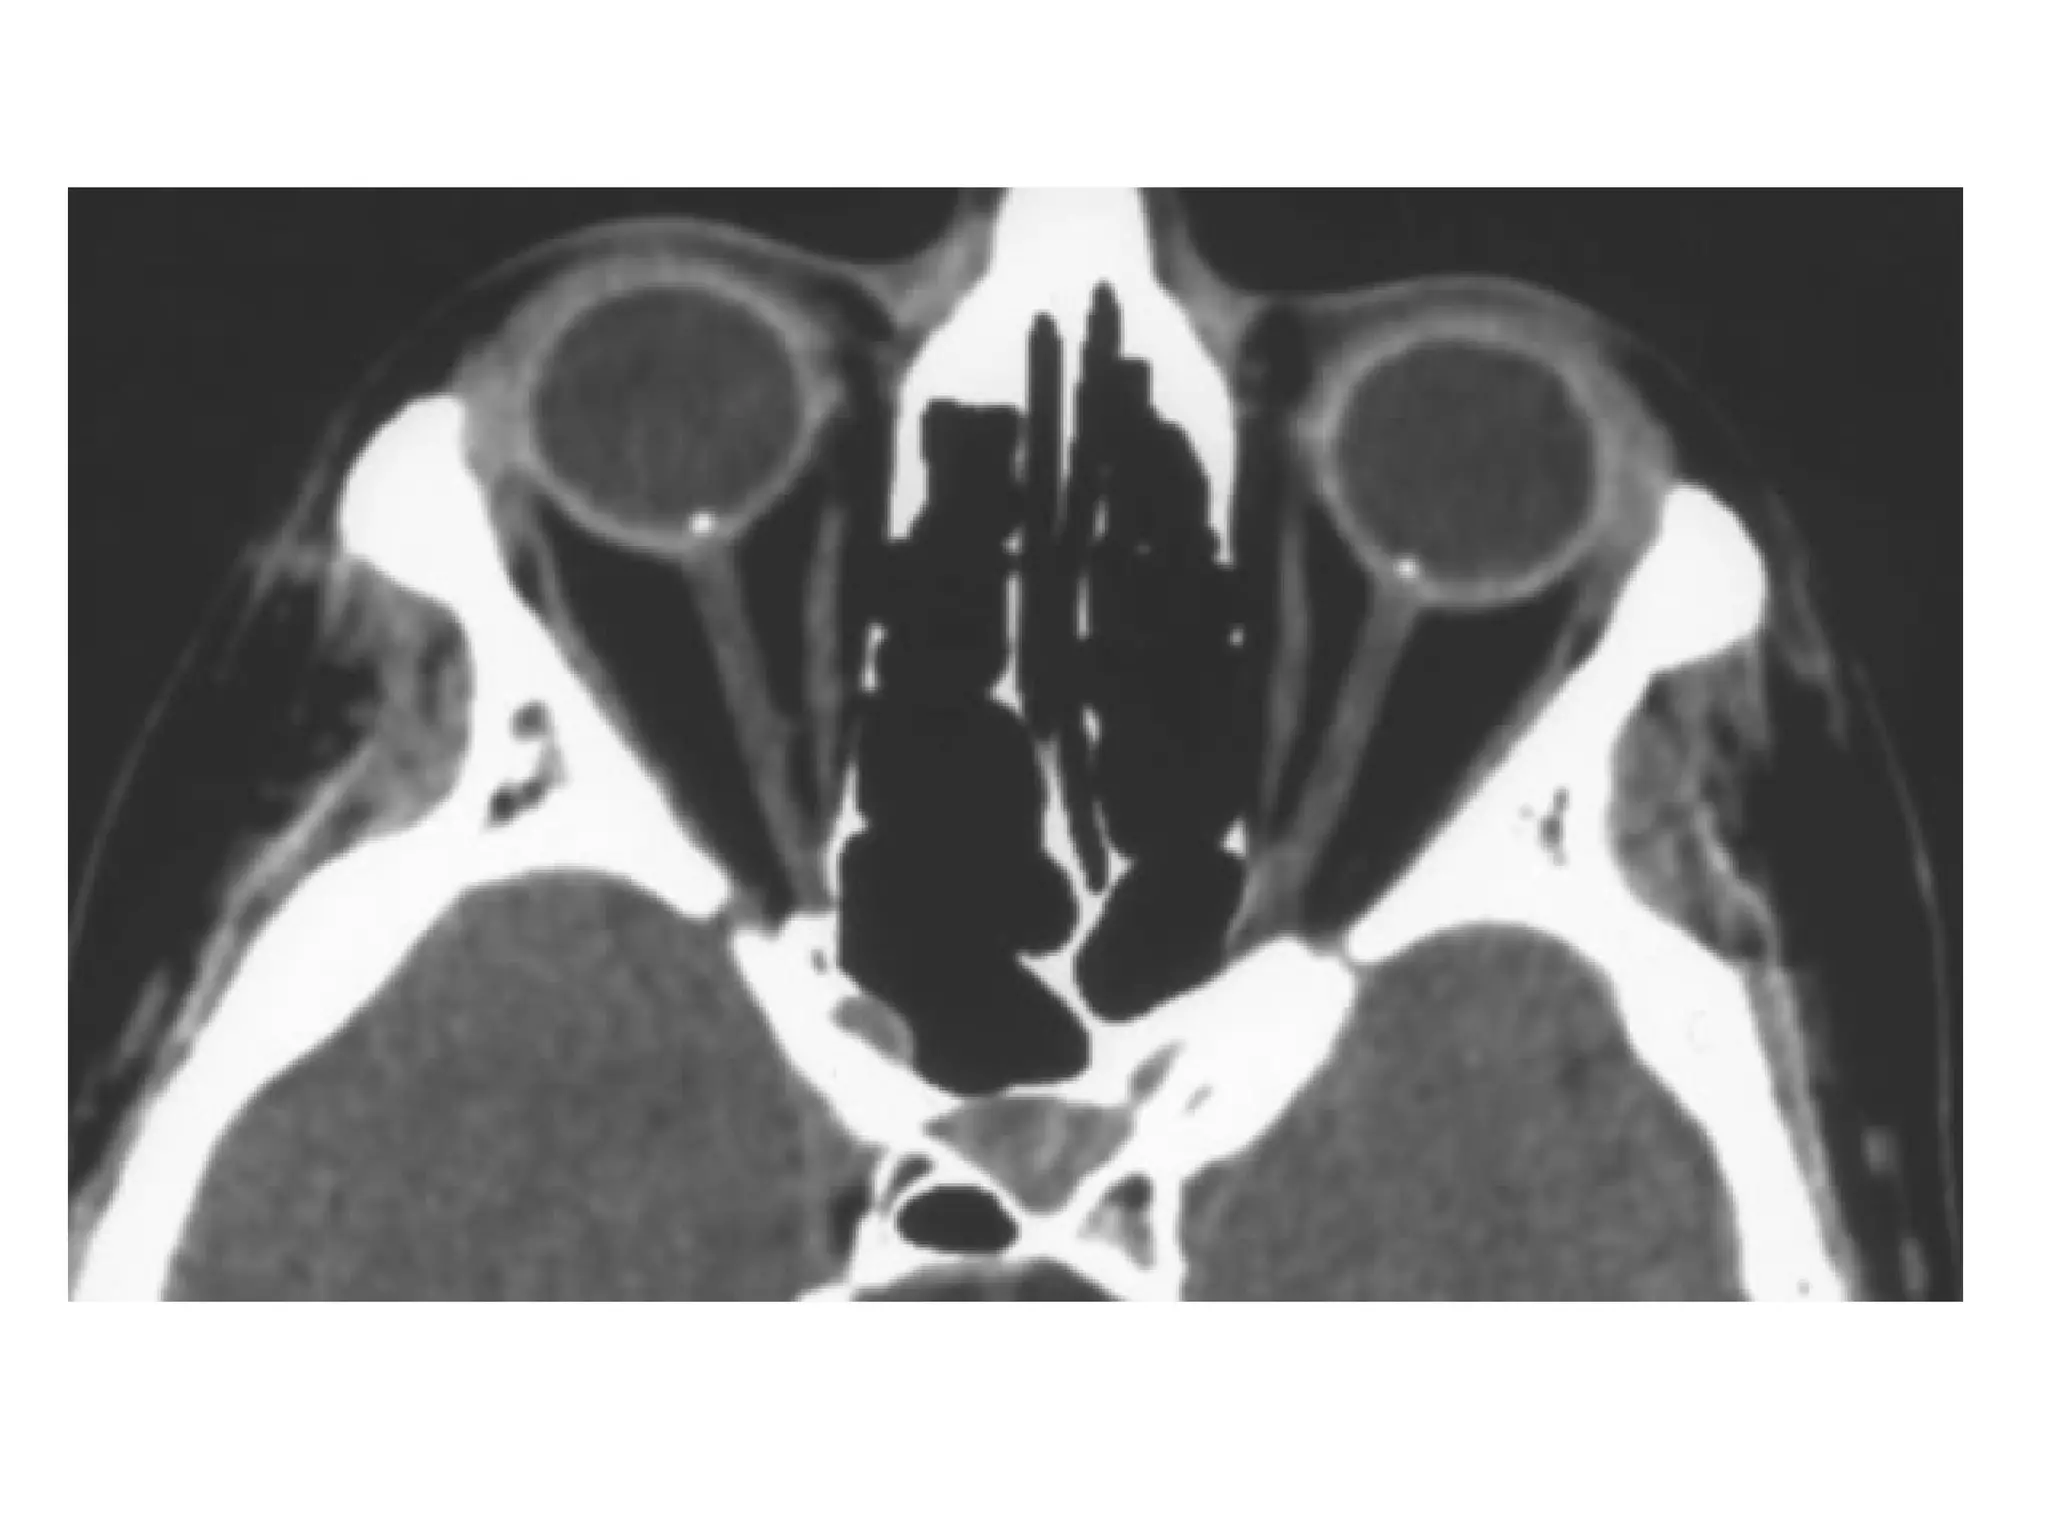

-CT findings suggestive of an open-globe injury include

a change in globe contour, an obvious loss of

volume, the “flat tire” sign, scleral discontinuity,

intraocular air, and intraocular foreign bodies

-Posterior movement of the lens enlarges or deepens

the anterior chamber, a deep anterior chamber has

been described as a clinical finding in patients with a

ruptured globe and can also be a useful clue on CT

image